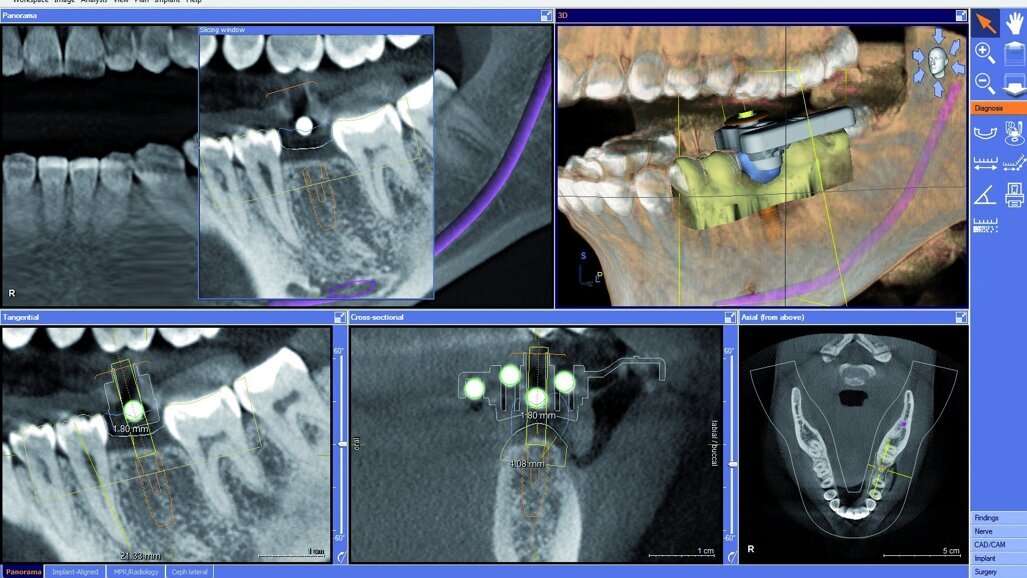

La patiente a été examinée au moyen du scanner intra-oral CEREC Bluecam et un plan de traitement a été élaboré pour la dent manquante. Le scanner GALILEOS (Sirona) a été utilisé pour réaliser une tomodensitométrie volumique à faisceau conique (CBCT) de la mâchoire inférieure. Une collimation du faisceau a permis de prendre la zone édentée, recouverte par un corps de référence CEREC Guide, maintenu dans un matériau thermoplastique.

Le corps de référence a été identifié par le logiciel, et une pose implantaire virtuelle ainsi que le projet de couronne CEREC ont été importés dans le programme. Cette procédure permet au clinicien de procéder à la pose virtuelle de l’implant, en référence à la position idéale définitive de la couronne. Dans cette étude de cas particulière, il a été jugé qu’une restauration vissée serait souhaitable ; par conséquent, le trou d’accès à la vis de l’implant a été positionné au centre de la couronne.

Dans le cas présenté, le guide chirurgical a permis la pose d’un implant OsseoSpeed TX (DENTSPLY Implants) (4,0 x 11 mm). La patiente a été préparée selon un protocole de soins stériles standard et la zone a été anesthésiée comme pour une pose implantaire habituelle. Le guide chirurgical s’adapte étroitement sur les dents existantes, en épousant les surcontours ainsi que les sous-contours et devient de la sorte, une plateforme très stable à travers laquelle il est possible de fraiser. Nous avons utilisé un emporte pièce pour tissus mous de la gamme Facilitate, pour éliminer le tissu mou en surface, et suivi une procédure de perçage standard en nous servant des clés de perçage Sirona.

embedImagecenter("Imagecenter_1_901",901, "large"); Une stabilité primaire élevée (40 Ncm) a été obtenue et un pilier de cicatrisation de 4 mm a été placé immédiatement. La cicatrisation s’est déroulée sans douleur, gonflement et gêne. La radiographie long cône péri-apicale prise après l’intervention, correspondait parfaitement au plan de traitement préopératoire, indiquant une angulation idéale de l’implant pour une couronne vissée. Après deux mois de cicatrisation, une empreinte sur implant à ciel ouvert (pickup) avec porte-empreinte fenestré a été prise, et un modèle a été élaboré en utilisant une réplique Astra Tech. Un pilier standard en métal a été inséré dans la réplique et réduit pour laisser un espace de 3 mm par rapport au plan d’occlusion. Il a ensuite été poudré et scanné par CEREC Bluecam, et un bloc IPS e.max CAD C 14 a été usiné pour fabriquer la couronne.